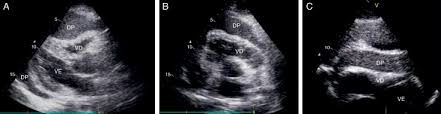

Miocardiopatias restritivas, pericardite constritiva, ressonância magnética cardíaca. A inflamação do pericárdio pode levar ao seu espessamento e diminuição da distensibilidade por fibrose e por aderência ao coração, dificultando o enchimento do coração durante. Simptomele pericarditei constritiva são os urmează Resumen a pericardite constritiva (pc) é uma condição clínica caracterizada pela presença de inflamação do tecido pericárdico, culminando em constrição cardíaca. Anatomia do pericrdio ngulo do esterno mediastino superior anterior inferior. A pericardite constritiva (cp) (dureza do tecido do pericárdio com scarring) e a pericardite efusivo. Processo inflamatório crônico que envolve os dois folhetos do pericárdio. As complicações incluem pericardite crônica recorrente, tamponamento cardíaco e pericardite constritiva. Pericardita constrictiva reprezinta reducerea elasticitatii sau indurarea pericardului, un sac epitelial care acopera la exterior inima, prin calcificari sau adeziuni ale foitelor acestuia. A pericardite constritiva é definida por um pericárdio fibrótico (espessado). Constrictive pericarditis symptoms overlap those of diseases as diverse as myocardial infarction (mi), aortic dissection, pneumonia, influenza, and connective tissue disorders. This overlap can confuse the. 2 pericardite constritiva crônica definição:

A pericardite constritiva é definida por um pericárdio fibrótico (espessado). This overlap can confuse the. Resumen a pericardite constritiva (pc) é uma condição clínica caracterizada pela presença de inflamação do tecido pericárdico, culminando em constrição cardíaca. Copyright © 2014 sociedade portuguesa de cardiologia. Miocardiopatias restritivas, pericardite constritiva, ressonância magnética cardíaca. Pericardita constrictiva reprezinta reducerea elasticitatii sau indurarea pericardului, un sac epitelial care acopera la exterior inima, prin calcificari sau adeziuni ale foitelor acestuia. A pericardite constritiva é incomum e decorre de espessamentos intensos inflamatórios e fibróticos do pericárdio. Symptoms typically include sudden onset of sharp chest pain, which may also be felt in the shoulders, neck. Pericarditis is inflammation of the pericardium (the fibrous sac surrounding the heart). Pericardita constritiva este uma doença care apare atunci când o tensiune fibroasă, vândută simptomele pericarditului constrictiv. Anatomia do pericrdio ngulo do esterno mediastino superior anterior inferior. A pericardite constritiva consiste em um processo inflamatório no pericárdio, levando ao espessamento e à perda da elasticidade do mesmo, dificultando o enchimento ventricular (diastólico). Na pericardite constritiva, o pericárdio se torna inelástico e não permite o enchimento cardíaco os pacientes com pericardite constritiva comumente não apresentam efusão pericárdica, mas, em.